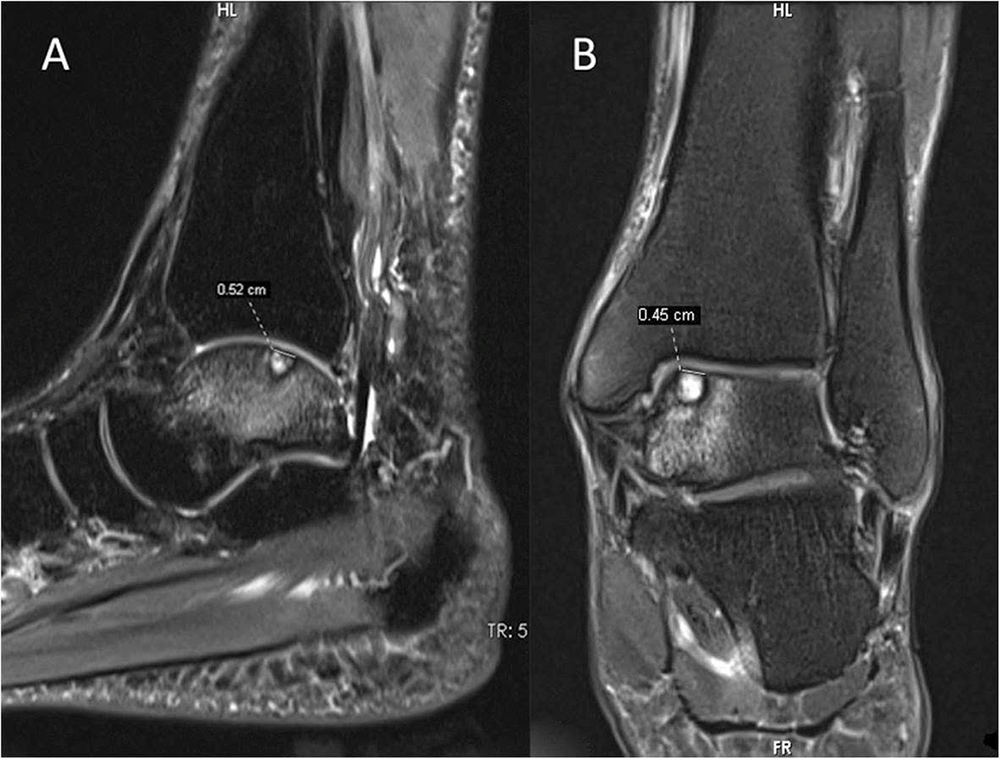

Tuy nhiên, kết quả MRI cổ chân trái cho thấy bệnh nhân có tổn thương sụn, xương sên, kèm phù nề nhẹ tủy xương xung quanh, chẩn đoán viêm sụn tách rời xương sên (OCD cổ chân). Đây là dạng tổn thương thường gặp ở người trẻ, đặc biệt là những người chơi thể thao có động tác xoay cổ chân, bật nhảy và đổi hướng đột ngột lặp đi lặp lại.